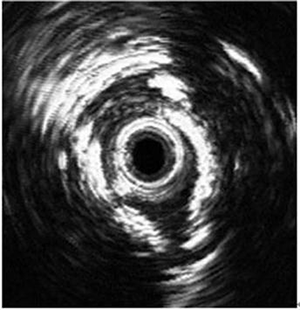

血管内超声(IVUS)对冠脉进行切面显像,不仅可观察到管壁结构和管腔形态,还可准确地测量血管直径、管腔面积和斑块面积,明确斑块的性质和偏心程度,明确血管造影中等程度冠脉狭窄病变的性质、严重性和稳定性,指导进一步的治疗。

从血管腔内显示冠状动脉血管的横断面,不但显示冠状动脉管腔的狭窄情况,还能了解冠状动脉血管壁的病变,包括斑块的性质、斑块破裂的位置、有无血栓形成等,还可以发现介入术后支架贴壁情况,是否有夹层、血肿、穿孔等并发症,尤其在左主干病变的介入治疗中,发挥非常重要的指导作用。